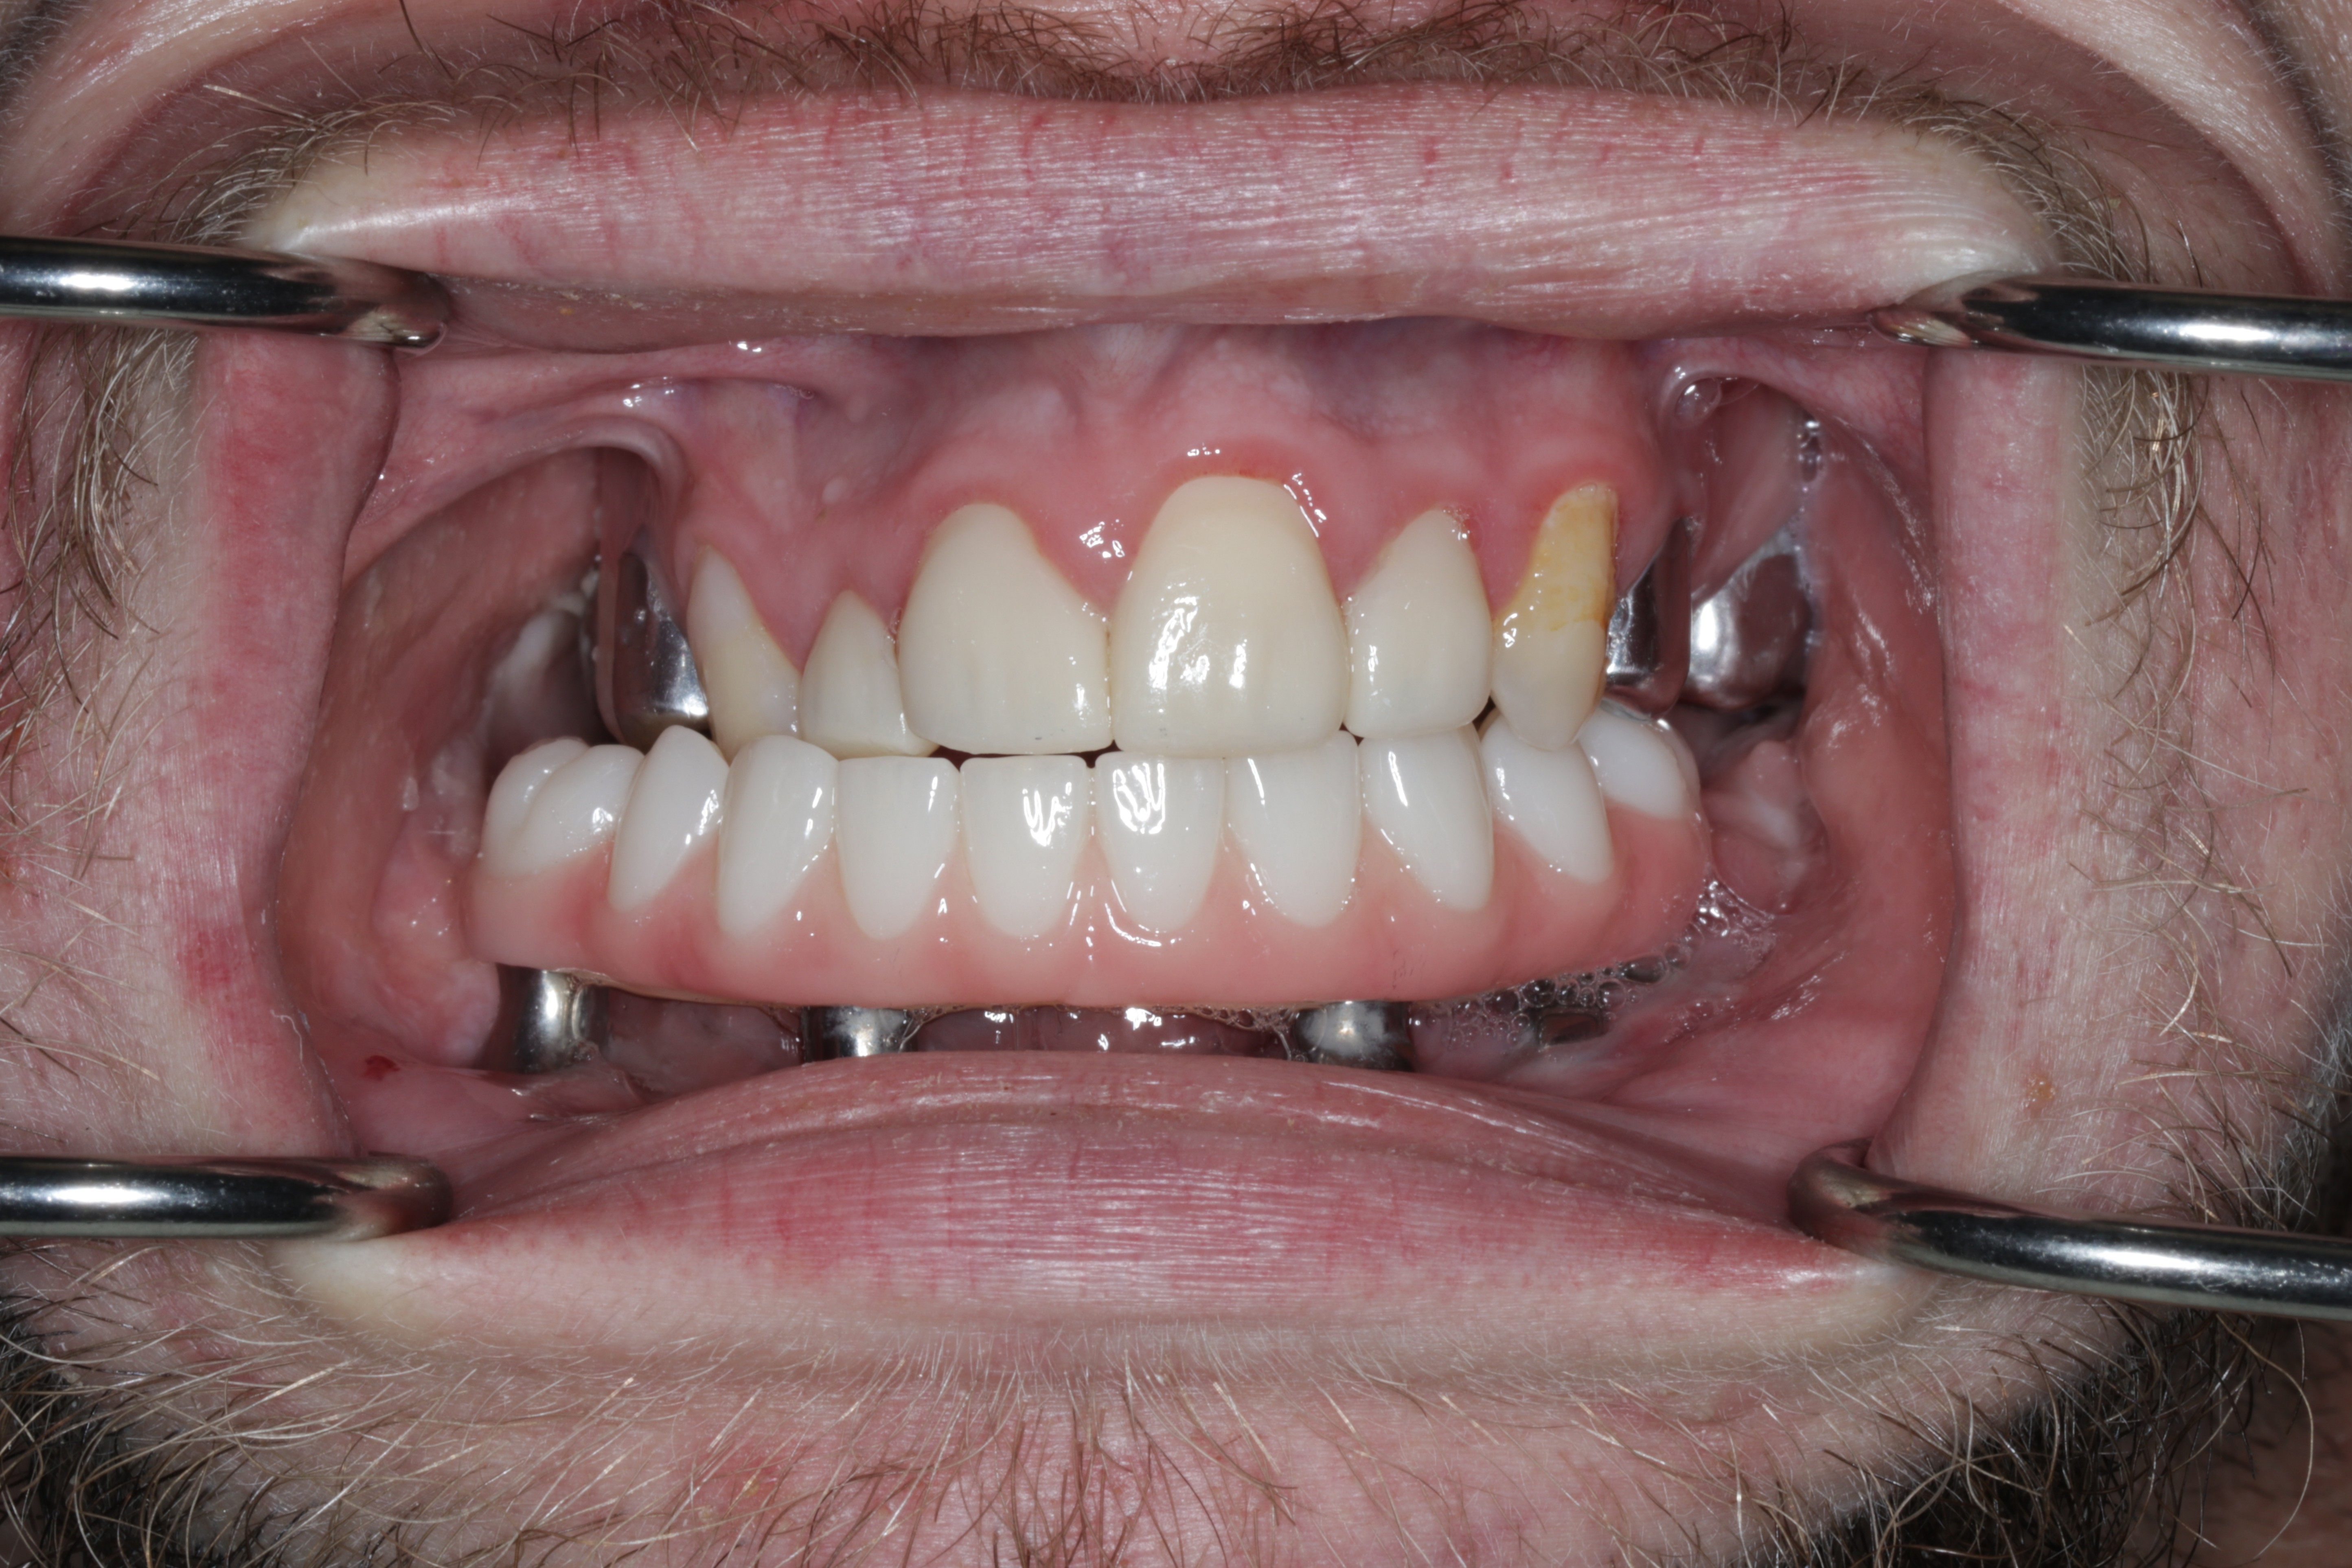

A 21-year-old male with CCMS presented with complete mandibular edentulism, severe mandibular atrophy, and limited oral opening. Retained maxillary dentition was present.

Records for this patient were collected using a dual-scan CBCT and intraoral scanning. A surgical planning session was completed with KLS Martin for the fabrication of a CAD-CAM subperiosteal implant system with immediate loading of a mandibular prototype (Figs 2-5).

A custom occlusal splint confirmed mount and prosthetic space. The site was closed with resorbable sutures intraorally and plain gut at trocar sites. Recovery was uneventful, and the patient progressed to prosthetic rehabilitation (Figs 9 and 10).

Maxillary scanning was performed after prototype removal. Bite registration scans were captured after reseating the prototype and verifying occlusion. An updated prototype was fabricated, adjusted minimally, and worn for four weeks before fabrication of final prothesis.

The refined prototype was rescanned on the back-pour cast, and a definitive monolithic implant supported fixed zirconia prosthesis was fabricated and successfully delivered (Figs 16 and 17).